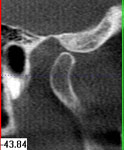

Im folgendem sehen Sie die Darstellung eines Teils des menschlichen Schädels mit Lokalisation des Nervkanales.

Sagittalansicht |